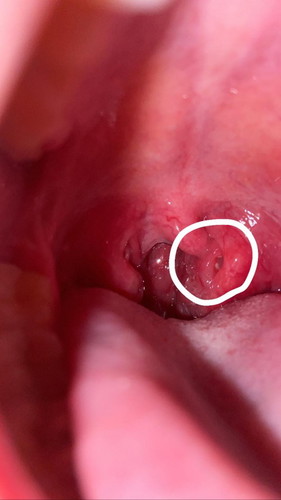

เป็นที่ในคอคะ

เป็นครั้งที่สองแล้วคะข้างๆในคอจะมีเสดข้าวเข้าไปยูในรูคะไม่มีกลิ่นไม่เจ็บ เกิดจากอะไรคะ

ทอลซิลค่ะ คือเศษอาหารเข้าไปทำให้เกิดกลิ่นปากได้ค่ะ

เขาเรียกทอลซิลค่ะ